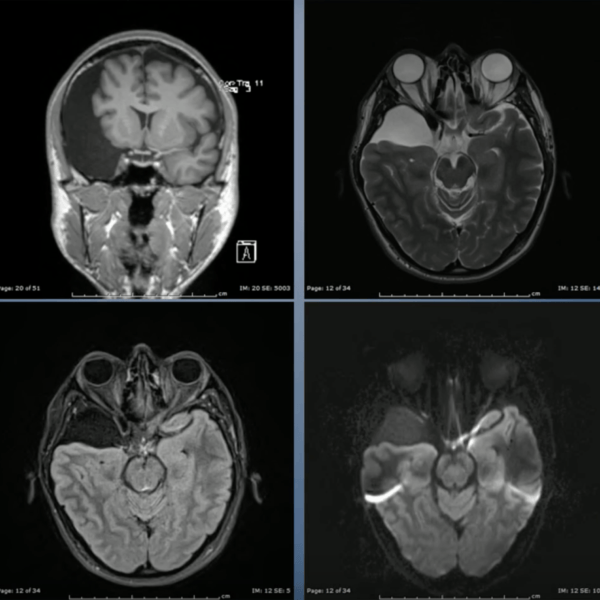

Arachnoid Cysts

Arachnoid cysts are fluid-filled sacs that develop between the brain or spinal cord and the arachnoid membrane — one of the three protective layers surrounding the brain and spinal cord. These cysts are filled with cerebrospinal fluid (CSF) and are often discovered incidentally during brain imaging. While many arachnoid cysts remain harmless, some can grow large enough to cause pressure on surrounding structures, leading to neurological symptoms that may require treatment.

• Magnetic Resonance Imaging (MRI) — the most accurate imaging tool to define the cyst’s location and size.